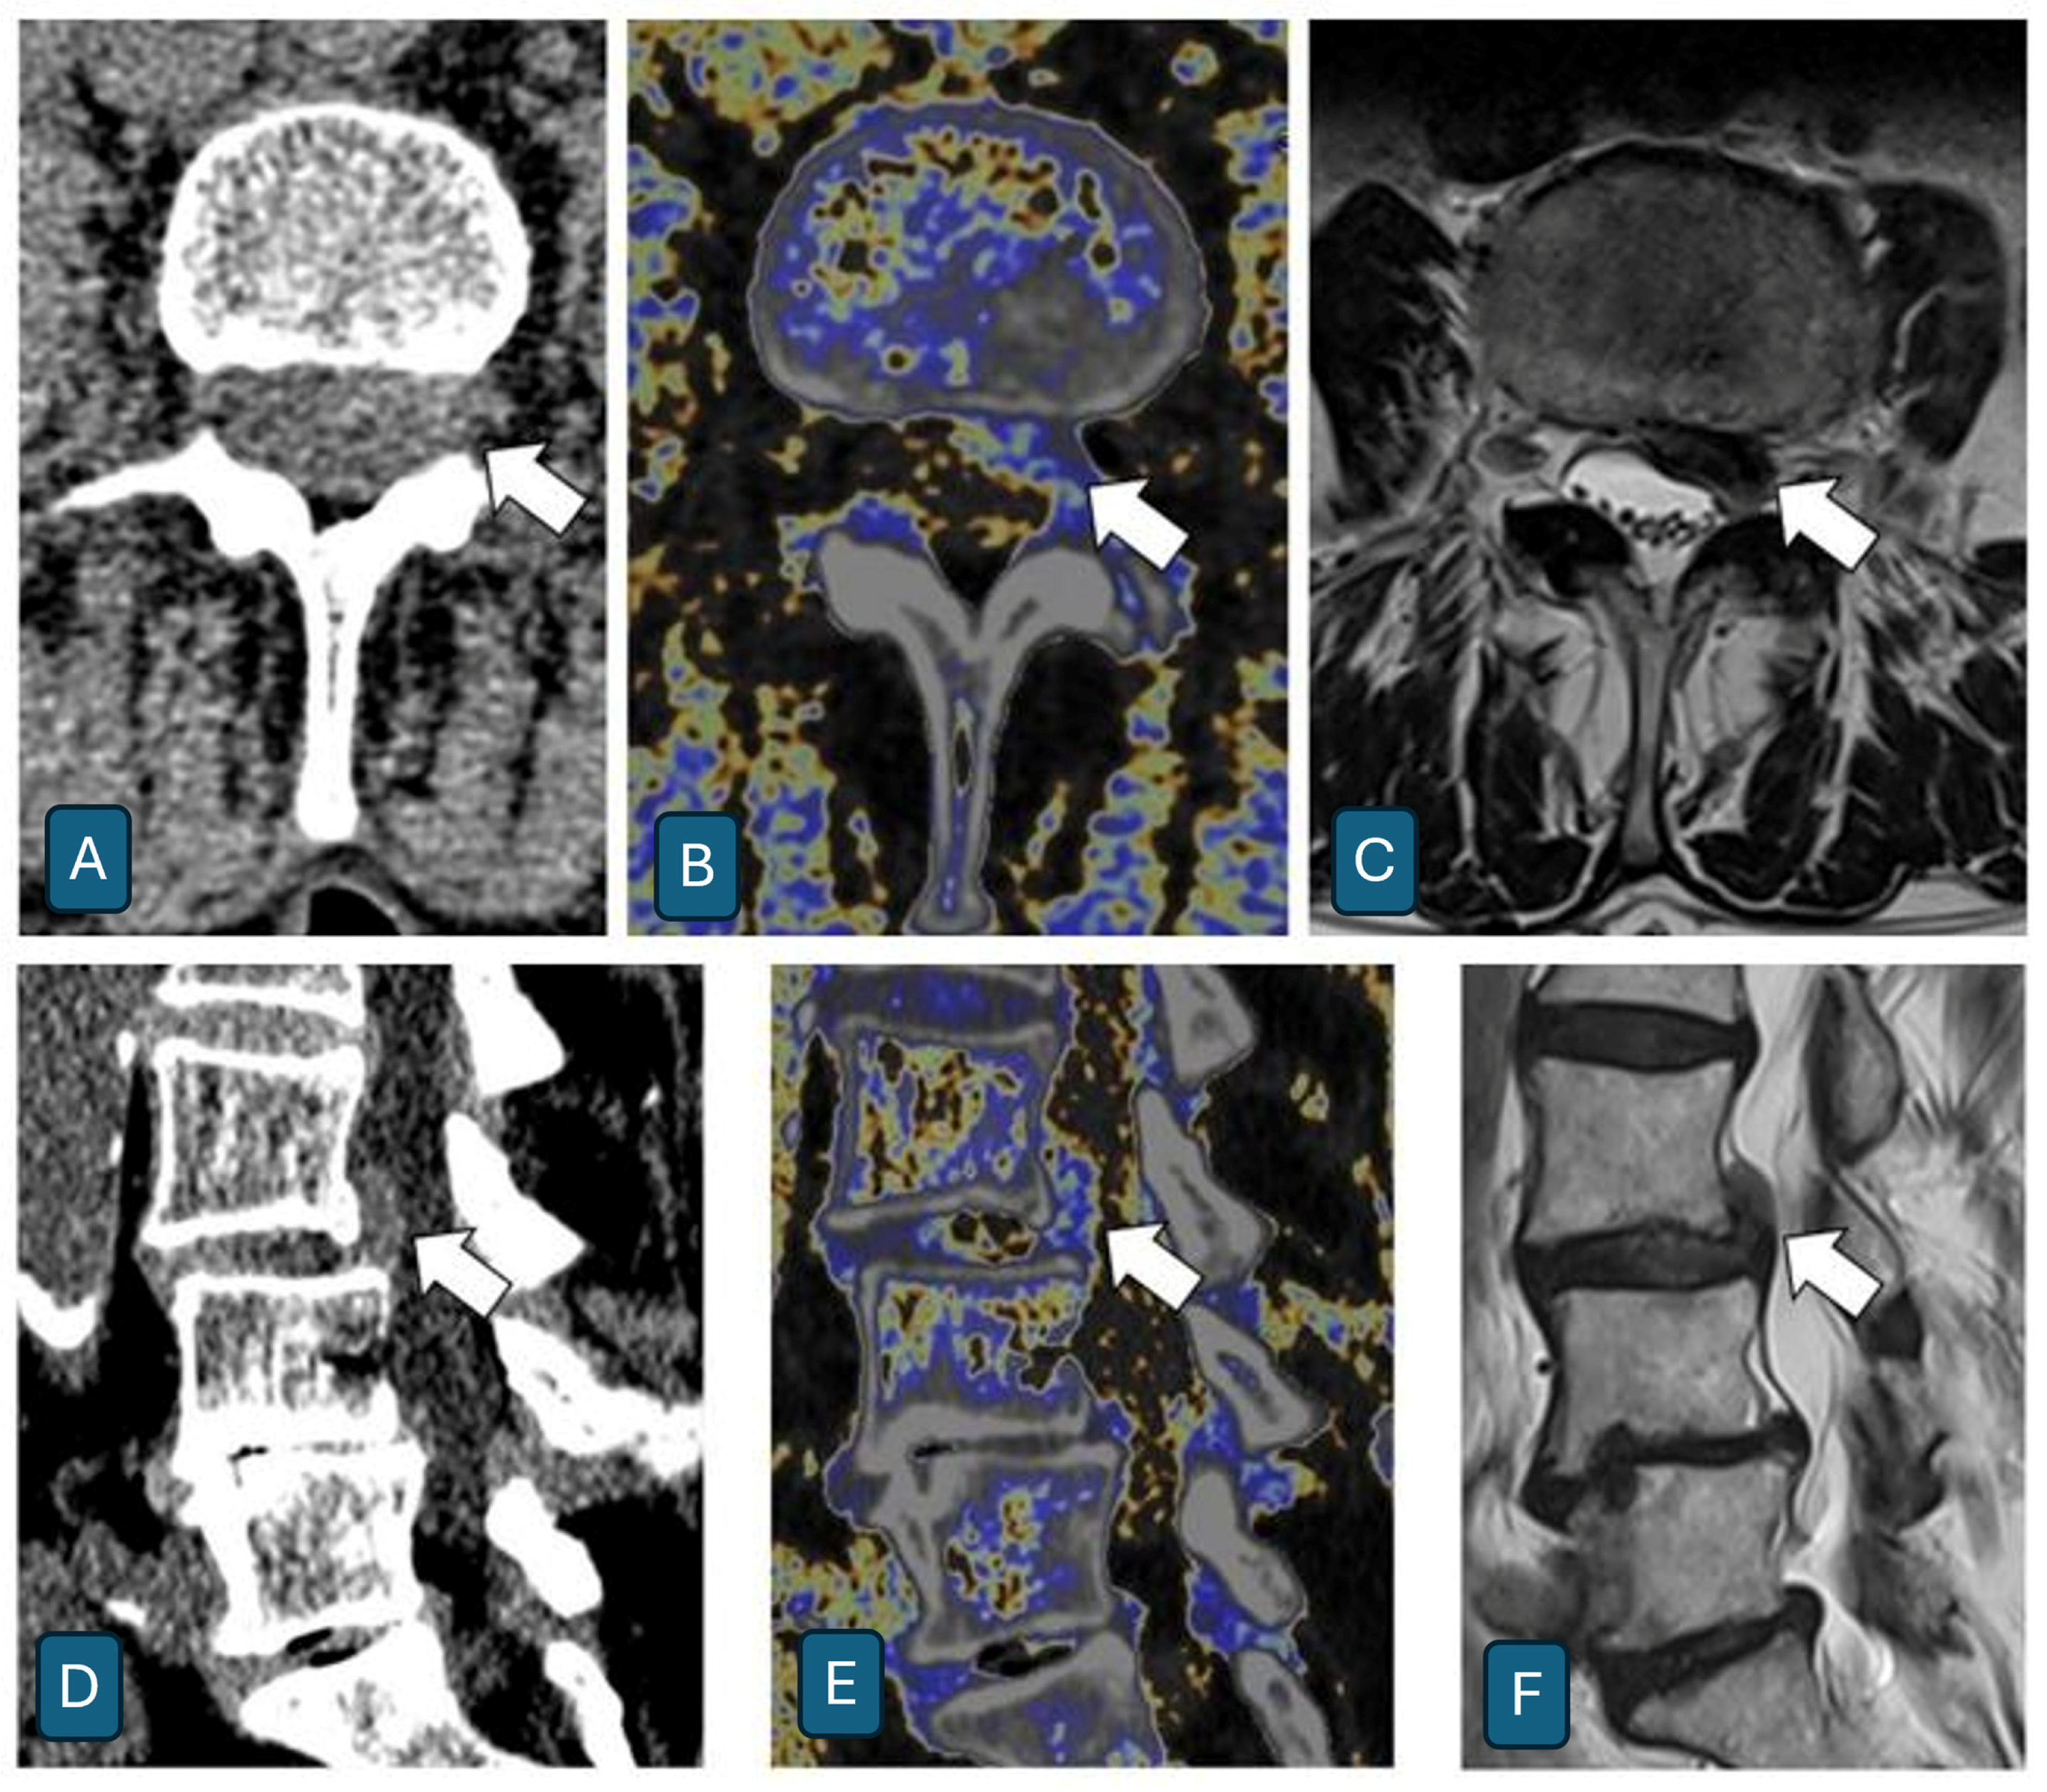

Assessment of Intervertebral Lumbar Disk Herniation: Accuracy of Dual-Energy CT Compared to MRI

- Booz, C.; Nöske, J.; Martin, S.S.; Albrecht, M.H.; Yel, I.; Lenga, L.; Gruber-Rouh, T.; Eichler, K.; D’Angelo, T.; Vogl, T.J.; et al. Virtual Noncalcium Dual-Energy CT: Detection of Lumbar Disk Herniation in Comparison with Standard Gray-scale CT. Radiology 2019, 290, 446–455. [Google Scholar] [CrossRef] [PubMed]